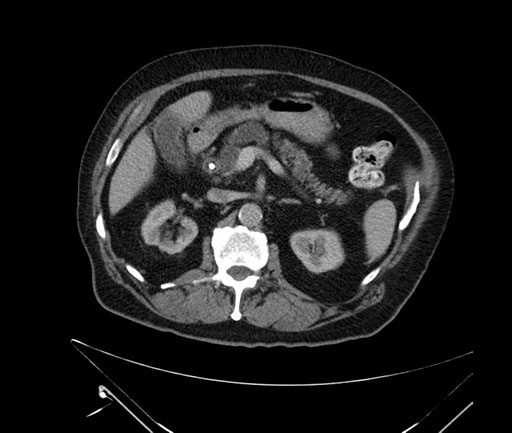

Whipple (pancreaticoduodenectomy) [case 7]

Axial - stented